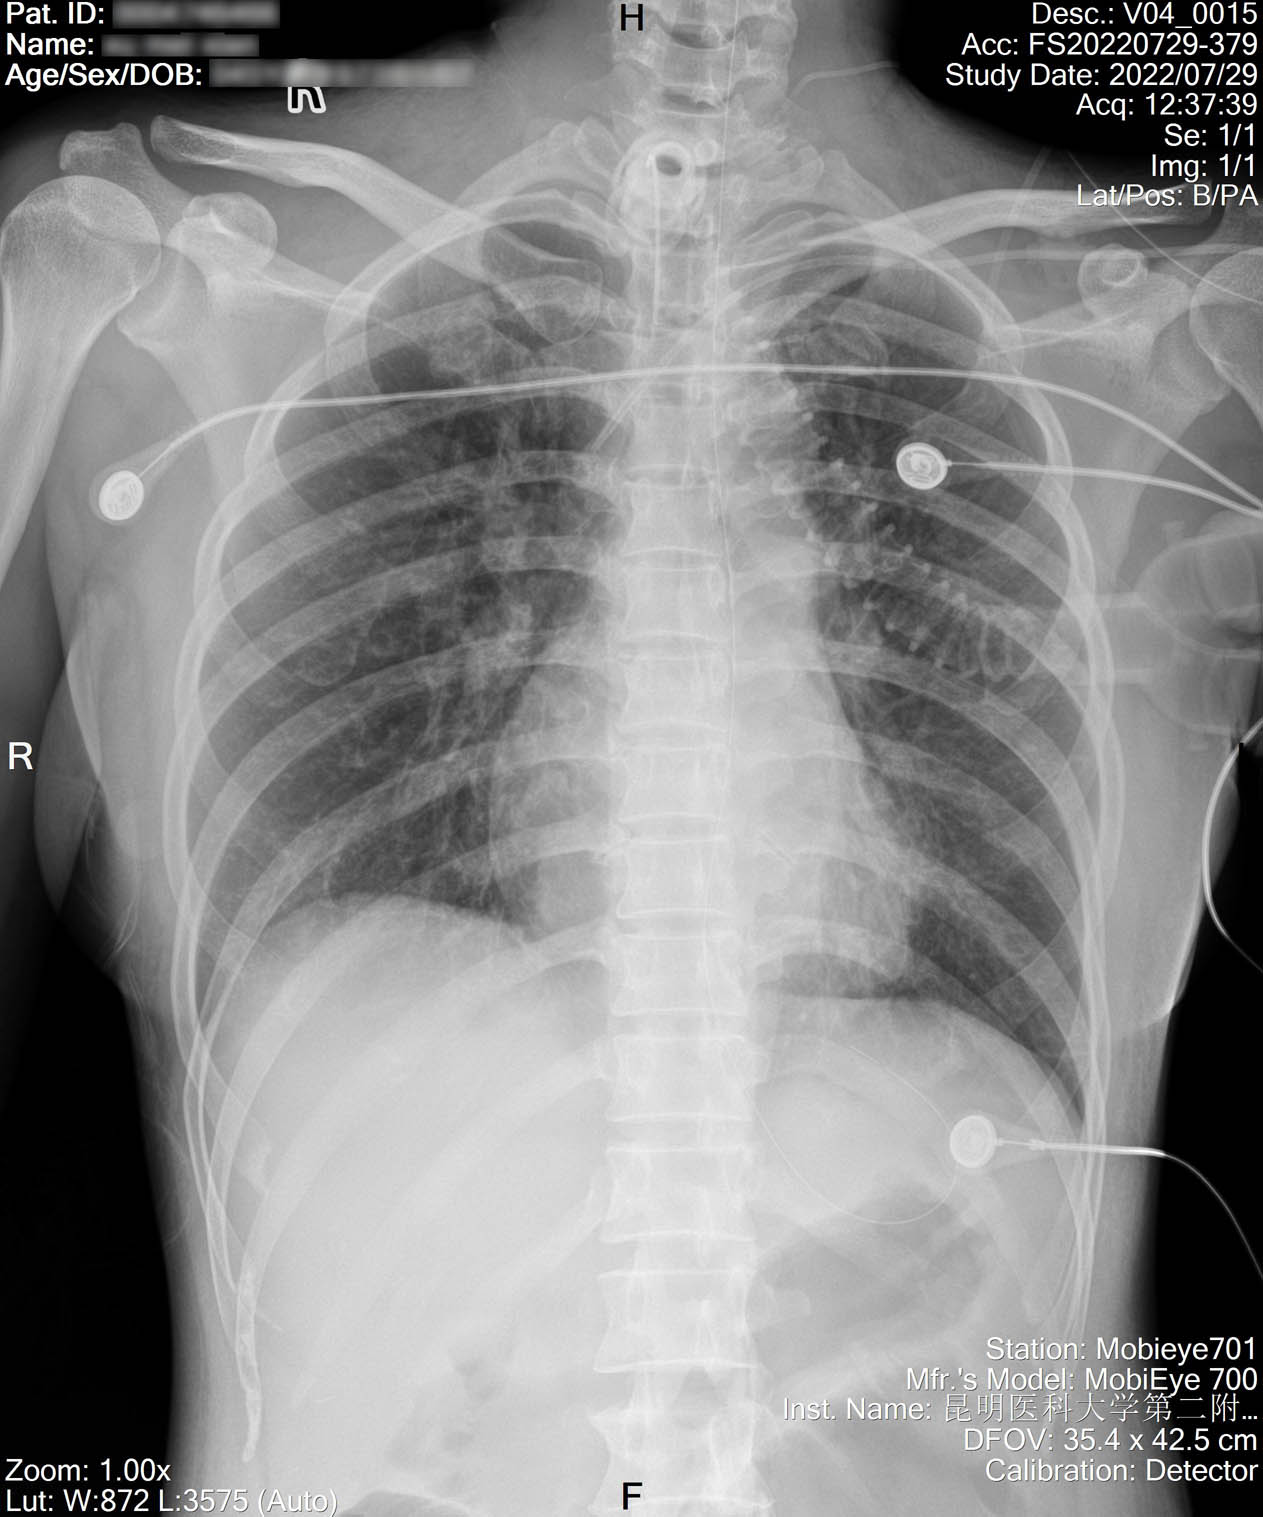

1.2.156.112536.2.560.184134135149163099.1425071090709.91.jpg

2022-07-16_胸片